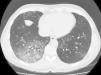

Se trata de un hombre de 53 años remitido a la consulta de neumología por clínica de 5 meses de evolución de tos con expectoración difícil y a veces hemoptoica y disnea progresiva a moderados esfuerzos. Era exfumador desde hacía 9 meses de 15 paquetes/año, sin referir otros hábitos tóxicos. No presentaba patología respiratoria previa ni exposición laboral a irritantes inhalados (profesión, aparejador). Su único antecedente patológico era que 8 meses antes había sido diagnosticado de hipertensión arterial ligera, sin lesión de órgano diana, y había iniciado tratamiento con eprosartán a dosis de 600mg cada 12h. A la exploración física estaba eupneico, con 16rpm, saturación transcutánea de oxígeno 98%, presión arterial 133/82mmHg, auscultación cardiaca normal y pulmonar con crepitantes en mitad inferior de hemitórax derecho. La radiografía de tórax presentaba pequeñas densidades bilaterales y la TC torácica mostraba un patrón en vidrio deslustrado en segmentos posterobasales del lóbulo inferior derecho y áreas parcheadas en lóbulo inferior izquierdo (fig. 1). El hemograma fue normal, y en la bioquímica solo destaca LDH 515 U/l. Estudios de autoinmunidad con factor reumatoide, ANA y ANCA negativos. Se realiza broncoscopia —que no muestra alteraciones—, cultivo bacteriano y micobacterias en el broncoaspirado negativo y citología bronquial normal. La biopsia transbronquial confirma el diagnóstico de neumonitis intersticial de predominio linfocitario, en ausencia de vasculitis, granulomas, eosinófilos y con escasa fibrosis del intersticio. La espirometría fue normal, pero la difusión pulmonar con helio (DLCO) fue del 41%. Pensando en la posibilidad de que la enfermedad pulmonar intersticial estuviera causada por el fármaco antihipertensivo que consumía el paciente, se retiró este medicamento. A los 20días el paciente experimentó una mejoría clínica significativa, cesando la tos y los esputos hemoptoicos y mejorando la disnea. A los 2meses de la retirada del fármaco el paciente se encontraba asintomático, y la TC torácica de control mostró una disminución del patrón intersticial con cambios que se limitan únicamente a la língula; su DLCO era del 70%. En la TC de control a los 6 meses se observó una resolución completa de la alteración intersticial, y la DLCO era normal. Dos años después de la supresión del fármaco el paciente sigue sin alteraciones clínicas, funcionales ni radiológicas.